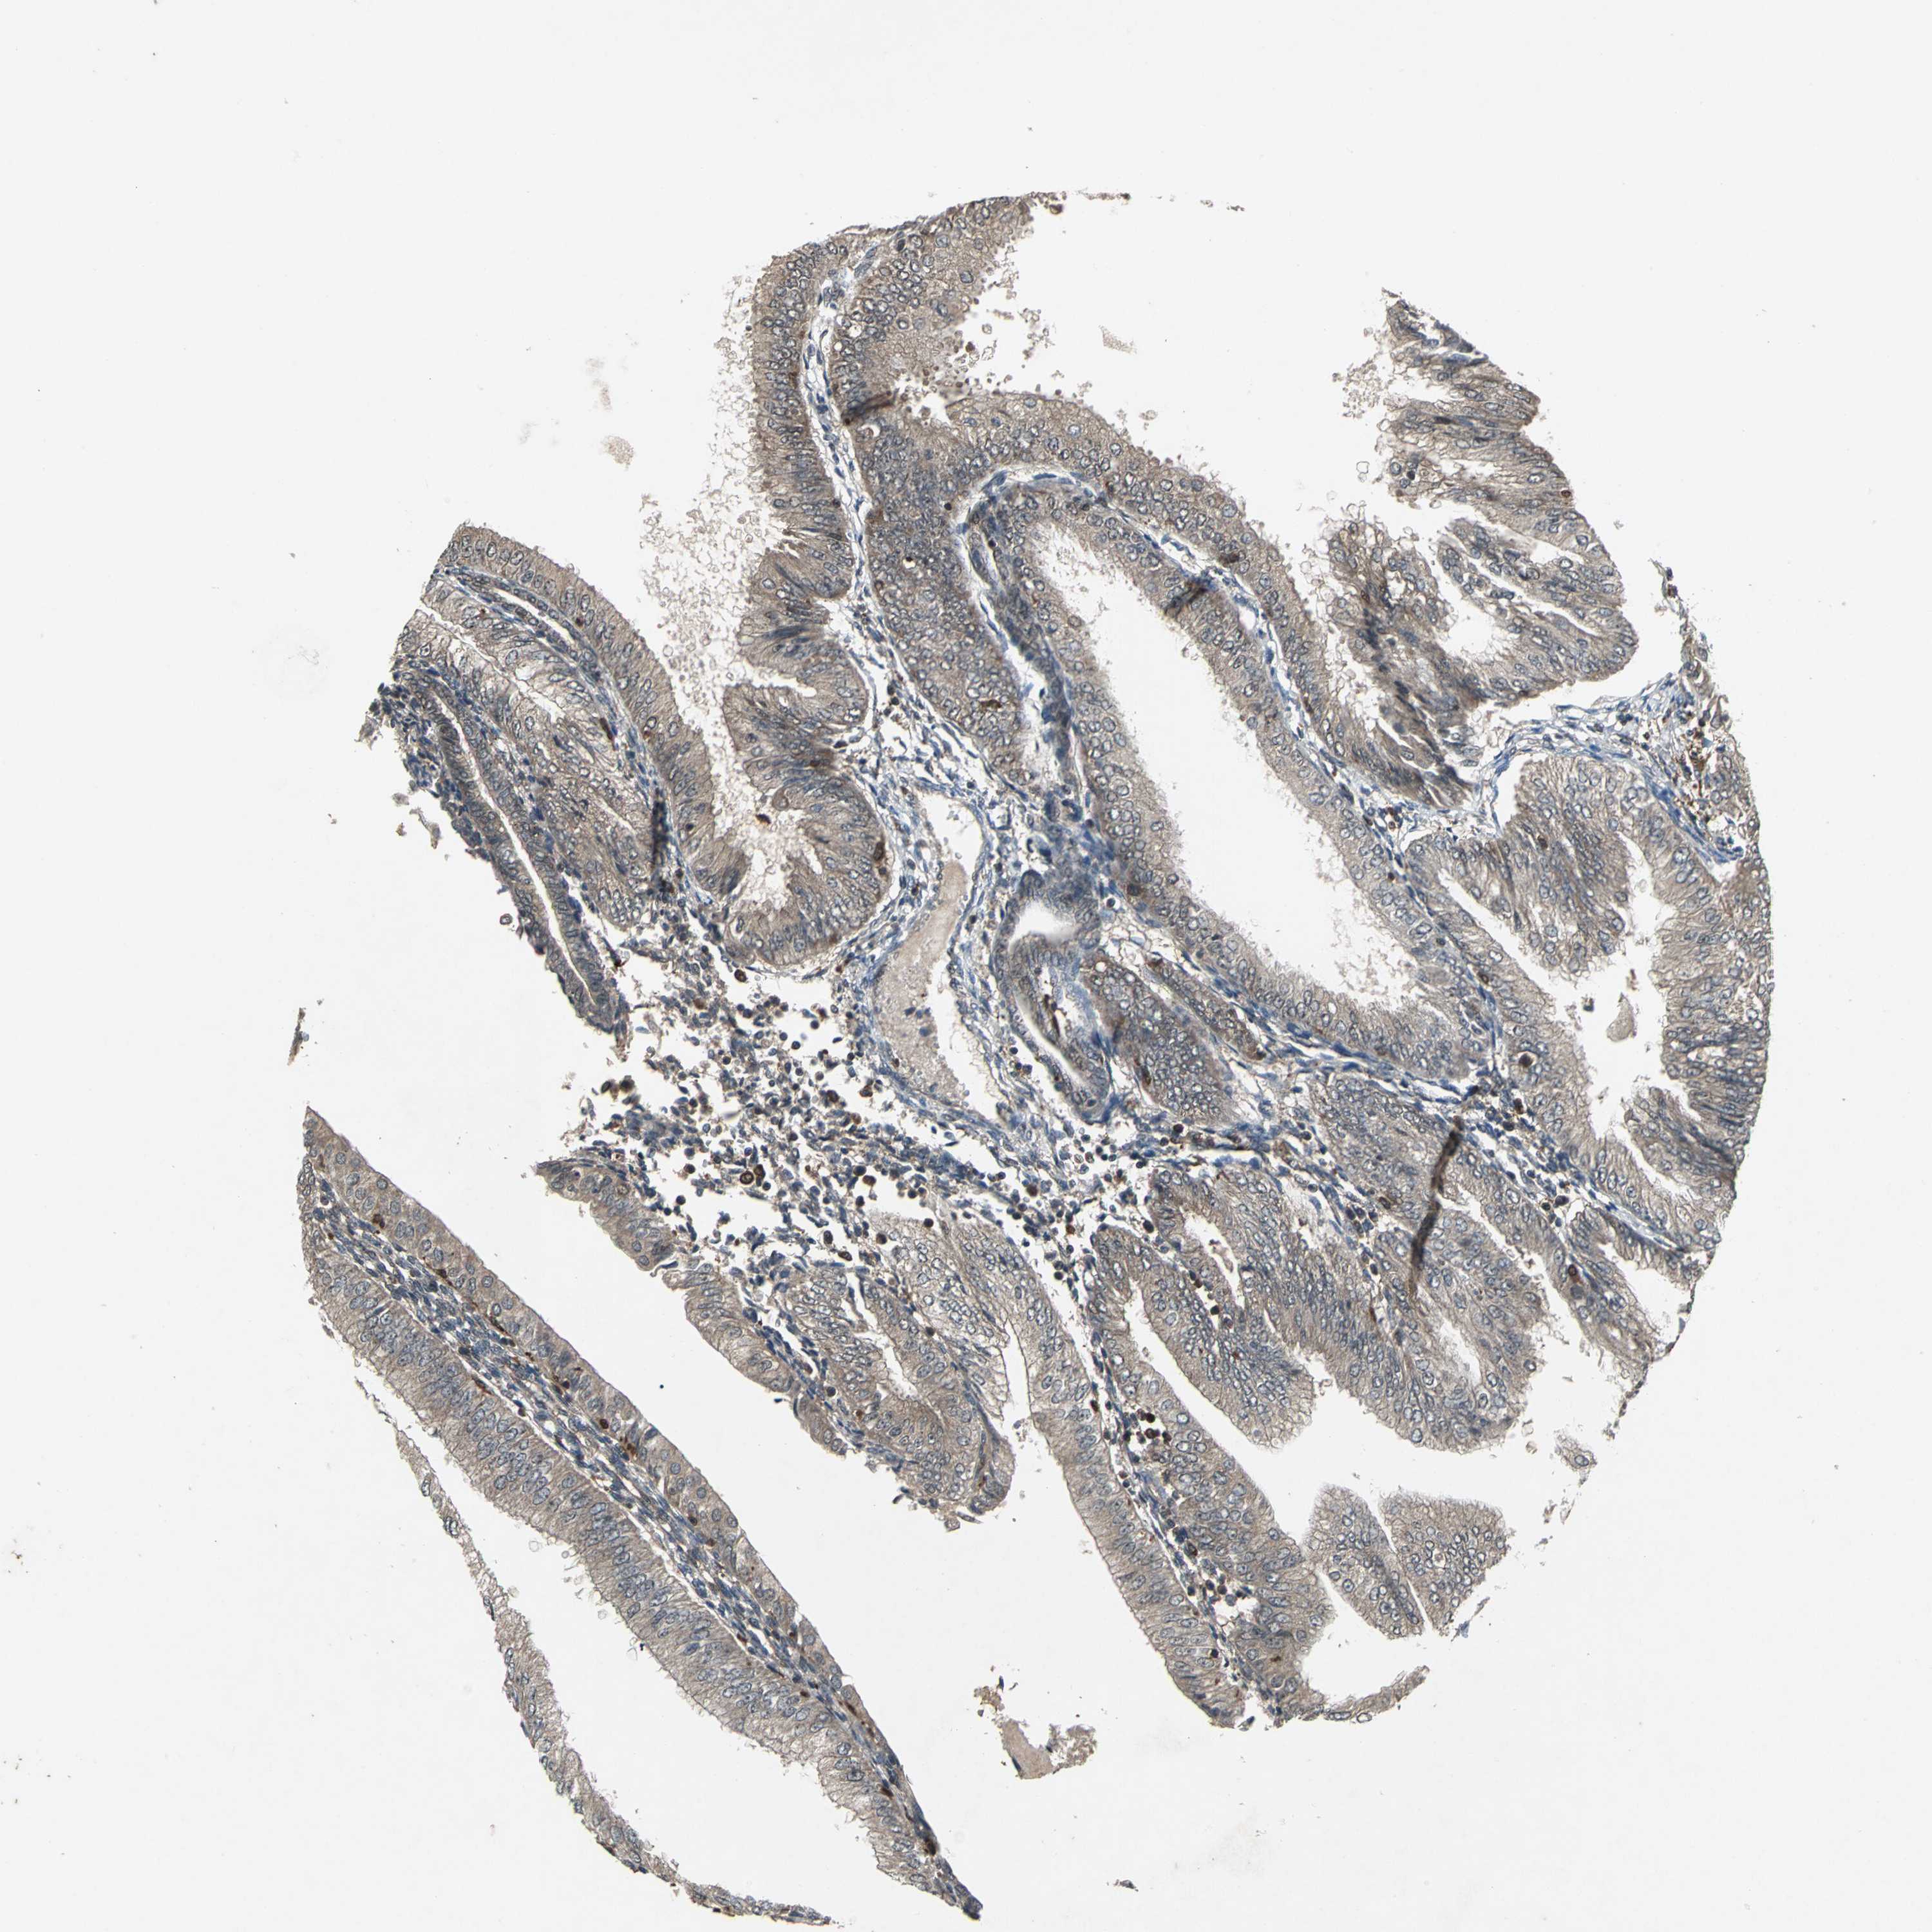

ENDOMETRIAL CANCER - Protein expressioni

A mouse-over function shows sample information and annotation data. Click on an image to view it in a full screen mode. Samples can be filtered based on level of antibody staining by selecting one or several of the following categories: high, medium, low and not detected. The assay and annotation is described here.

Note that samples used for immunohistochemistry by the Human Protein Atlas do not correspond to samples in the TCGA dataset.

Antibody stainingi

Antibody staining in the annotated cell types in the current human tissue is reported as not detected, low, medium, or high, based on conventional immunohistochemistry profiling in selected tissues. This score is based on the combination of the staining intensity and fraction of stained cells.

Each image is clickable and will lead to virtual microscopy that enables deeper exploration of all samples and also displays staining intensity scores, fraction scores and subcellular localization as well as patient and tissue information for each sample.

Antibody HPA049074

Antibody HPA054496

Antibody CAB006853

Antibody CAB015948

Staining

High

Medium

Low

Not detected

Intensity

Strong

Moderate

Weak

Negative

Quantity

>75%

75%-25%

<25%

None

Location

Nuclear

Cytoplasmic/membranous

Cytoplasmic/membranous,nuclear

Adenocarcinoma, NOS

Carcinoma, NOS

Adenocarcinoma, metastatic, NOS

Neoplasm, malignant, NOS